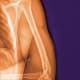

The UT Southwestern Department of Orthopaedic Surgery established a new section for Musculoskeletal Oncology that is currently made up of two surgeons: Alexandra (Alex) Callan, M.D. (section chief), and Robert (Bobby) Weinschenk, M.D. Together, they provide personalized care for patients with sarcomas and other bone or soft tissue tumors, serving at UT Southwestern, Simmons Comprehensive Cancer Center, and Parkland Memorial Hospital. Additionally, Dr. Callan treats pediatric patients at Children’s Health, where she is Director of Orthopaedic Oncology. Drs. Callan and Weinschenk are active members of the weekly Multidisciplinary Sarcoma Conference, which is designed to establish treatment plans for complex patients. The Musculoskeletal Oncology section uses innovative surgical techniques and reconstruction designs to optimize limb salvage surgery in sarcoma patients. For patients battling metastatic bone disease, the team’s goal is to decrease pain and help improve function to tolerate treatment in patients’ fight against cancer. The team is happy to evaluate all patients with complex problems – from benign or malignant soft tissue and bony tumors to complex total joint reconstructions or infections.